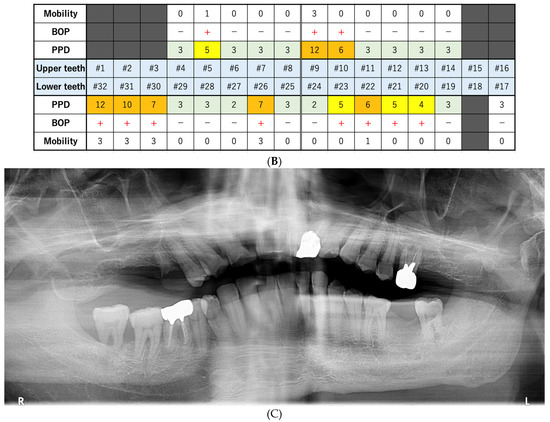

2.1. Day 1: First Examination